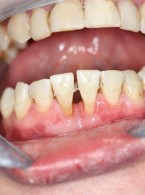

Dekoronacja

jako postępowanie zalecane w leczeniu pacjentów z postępującą pourazową infrapozycją zębów siecznych szczęki